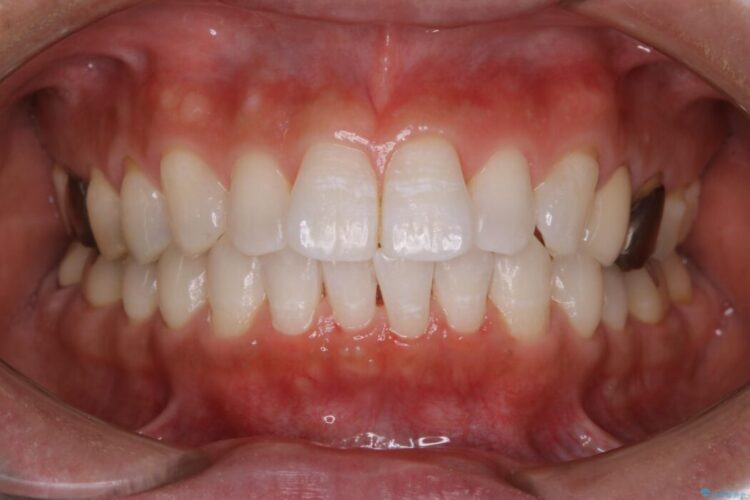

【30代男性】衝撃的なビフォーアフター!クリーニングで見違えるほどの白い歯に

【30代男性】衝撃的なビフォーアフター!クリーニングで見違えるほどの白い歯に ビフォー 【30代男性】衝撃的なビフォーアフター!クリーニングで見違えるほどの白い歯に アフター

歯の着色を綺麗にしたいとご来院されました。